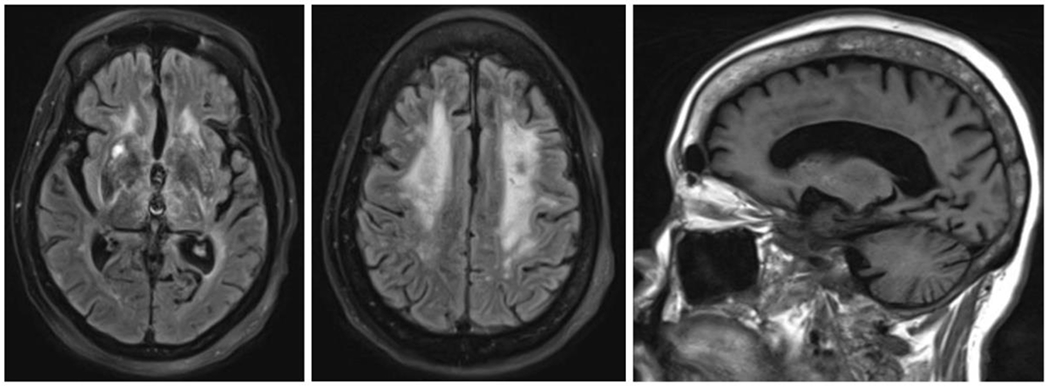

Cache Valley virus (CVV) is a mosquito-borne virus that is a rare cause of disease in humans. In the Fall of 2020, a patient developed encephalitis six weeks following kidney transplantation and receipt of multiple blood transfusions.

CVV was detected in CSF from the index patient by mNGS, and this result was confirmed by RT-PCR, viral culture, and additional whole genome sequencing. The organ donor and other organ recipients had no evidence of infection with CVV by molecular or serologic testing. Neutralizing antibodies against CVV were detected in serum from a donor of red blood cells received by the index patient immediately prior to transplant. CVV neutralizing antibodies were also detected in serum from a patient who received the co-component plasma from the same blood donation.

Our investigation demonstrates probable CVV transmission through blood transfusion. Clinicians should consider arboviral infections in unexplained meningoencephalitis after blood transfusion or organ transplantation. The use of mNGS testing might facilitate detection of rare, unexpected infections, particularly in immunocompromised patients.